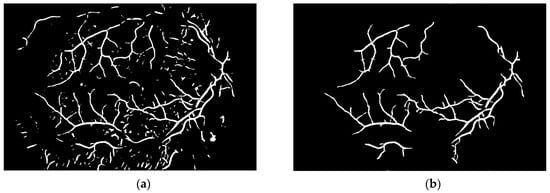

To obtain proper vascular patterns, a local entropy binarization algorithm was used to get proper white veins on a black background. However, this has caused a few small elements that do not belong to retinal veins to be shown in the image, alongside the marked veins. Additional elements are removed on the basis of their length. If they are too short (the length in pixel number is selected arbitrarily), they are deleted–we assume that these elements are not parts of real veins. The results of both of these steps are presented in Figure 13.

Via this step, the vascular pattern of the processed retina was obtained. In the form presented in Figure 13b, it will be applied to the obtained image after the preprocessing stage (Figure 8b). Both of these images are considered in the next module.

Figure 13. Image (a) after binarization and (b) after short vessel removal.